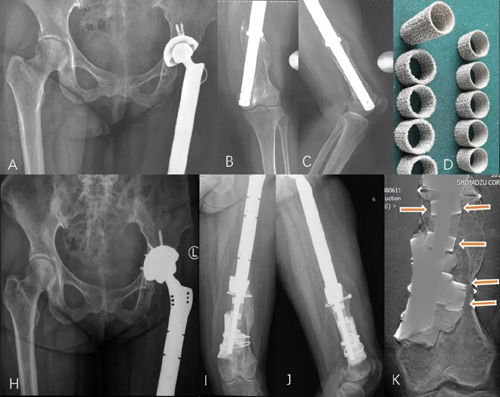

女,45岁,左股骨近端骨肉瘤行左股骨近端切除+左股骨近端肿瘤假体置换术后14年,可见假体松动下沉,采用沉管多孔金属圈(D)重建内壁后,患者目前随访3年余,假体固定良好,断层造影箭头指示处(K)可见多孔金属圈有骨长入,临床效果满意。

“沉管”骨内壁重建技术通过3D打印的多孔金属圈打入残端骨髓腔内获得初始压配固定,形成类似于松质骨结构的多孔“骨内壁”,为骨水泥假体的固定提供可交锁的多孔结构。而骨水泥-多孔金属圈-假体复合物又进一步为金属圈的骨整合提供了足够的初始稳定性, 经骨长入后多孔金属可以成为永久的“骨内壁”,获得生物学固定。因此该种“沉管” 骨内壁重建技术是一种同时构建骨水泥固定和生物学固定的混合固定(hybrid fixation)技术。

▲混合固定示意图,C1为骨水泥假体,C2为骨水泥层,C3为多孔金属圈的实心层,C2和C3之间示意有骨水泥渗入金属圈多孔层,C4示意骨小梁长入金属圈的多孔层获得生物固定,C5为皮质骨髓腔面 (引自文献:Huang Y, Zhou Y, Shao H, Yang D, Tang H, Guo S. A Novel Endosteal Reconstruction of the Femur from Distal Femoral Remnant Using 3D-Printed Titanium Rings: A Two-Case Report. JBJS Case Connect. 2021 Aug 27;11(3). doi: 10.2106/JBJS.CC.20.01038. PMID: 34449452.)。